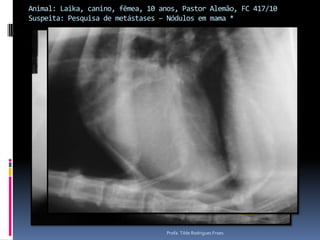

Animal: Laika, canino, fêmea, 10 anos, Pastor Alemão, FC 417/10Suspeita: Pesquisa de metástases – Nódulos em mama *Profa. Tilde Rodrigues Froes

Animal: Laika, canino,fêmea, 10 anos, Pastor Alemão, FC 417/10Suspeita: Pesquisa de metástases – Nódulos em mama *Profa. Tilde Rodrigues Froes